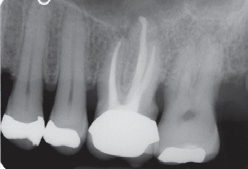

Ein 54-jähriger Patient wurde vom Hauszahnarzt mit der Bitte überwiesen, vor geplanter prothetischer Neuversorgung eine endodontische Revisionstherapie am Zahn 26 durchzuführen (Abb. 6). Der Zahn reagierte auf die Sensibilitätsprüfung mit CO2-Schnee negativ, auf Perkussion unauffällig. Die endodontische Diagnose lautete: Pulpastatus: pulpless and infected; periapikaler Status: asymptomatic apical periodontitis.

Nach Aufklärung des Patienten über die Behandlungsoptionen entschied er sich für die endodontische Revisionsbehandlung. Nach Infiltrationsanästhesie und Applikation von Kofferdam wurde unter dem OP-Mikroskop die Zugangskavität mit dem Diamantinstrument 15802 und anschließend dem EndoGuard angelegt. Die Darstellung des Pulpenkammerbodens und der Kanalorificien mit dem alten Obturationsmaterial erfolgte mit extralangen Rosenbohrern (Abb. 7).